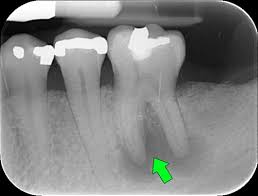

Bác sĩ tiến hành thăm khám tổng quát sức khỏe răng miệng, chụp phim X-quang quanh chóp hoặc X-quang toàn hàm (nếu cần thiết) ghi nhận đặc điểm, hình dạng của những răng cần nhổ và các răng xung quanh.

X- Quang quanh chóp   X- Quang toàn hàm

Từ đó, bác sĩ nhận định được mức độ khó dễ của ca tiểu phẫu. Điều này đặc biệt quan trọng đối với các ca nhổ răng khôn.